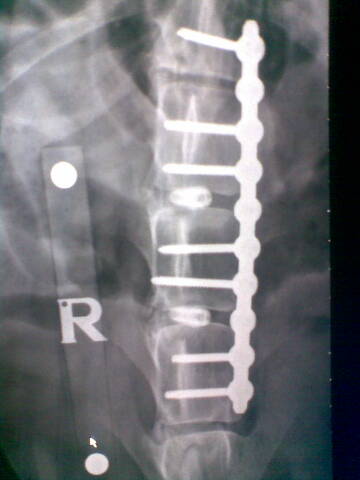

It was make or break. Noel said he could attempt something that had never been done before, the separating of discs from each other and the spinal chord via several screws inserted at a specific angle. These would give the spinal chord the room it needed to recover, or at least give it a better chance, although the procedure was a potentially a highly dangerous one and one that to Noel's knowledge had never been carried out before.

For those of you who are intrigued here's the actual miracle in place. Amazing, amazing people who do these things.